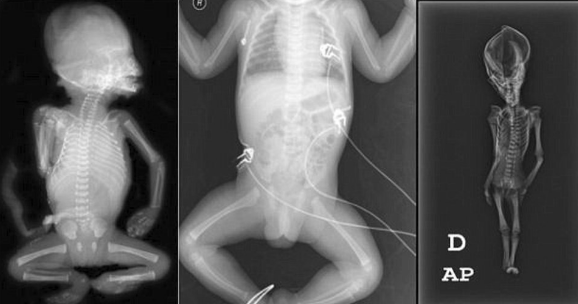

ŞİLİ'nin Atacama Bölgesi'nde bulunan, kafası koni şeklinde, 15 cm uzunluğundaki mumyanın üzerinde yapılan çalışmalar tamamlandı. Daha önce hakkında uzaylı mumyası olduğuna dair iddialar ortaya atılan mumyanın altından bir insanlık dramı çıktı.

2003 yılında Şili’de bulunan ve bir uzaylıya ait olabileceği iddia edilen, 15 cm uzunluğundaki mumyanın üzerinde yapılan yeni bilimsel çalışmanın sonuçları açıklandı. Uzaylı mumyası olduğu iddia edilen yaratık, Atacama bölgesinde deri bir çanta içerisinde terk edilmiş bir kilisede bulunmuştu.

15 HAFTALIK BİR CENİNE AİT; Uluslararası bir bilim ekibi 15 santimetre büyüklüğündeki mumya üzerinde yaptığı araştırmayı tamamladı ve mumyanın 15 haftalık bir cenine ait olduğunu açıkladı. Fakat geçtiğimiz aylarda yapılan bir başka araştırma ortaya daha farklı sonuçlar koymuştu.

California Üniversitesi, San Francisco Üniversitesi ve Stanford Üniversitesi tarafından “Ata” ismi verilen mumyaya yapılan DNA analizleri, ,gizemini uzun süre koruyan kalıntının, çeşitli genetik mutasyonlara uğramış, 6-8 yaşında olduğu tahmin tahmin edilen cüce bir kız çocuğuna ait olduğunu ortaya koymuştu. Yapılan bilimsel çalışmalar, çocuğun 40 yıl önce öldüğünü ve bugüne kadar tanımlanmamış olan gen bozukluklarına sahip olduğunu açığa çıkarmıştı.